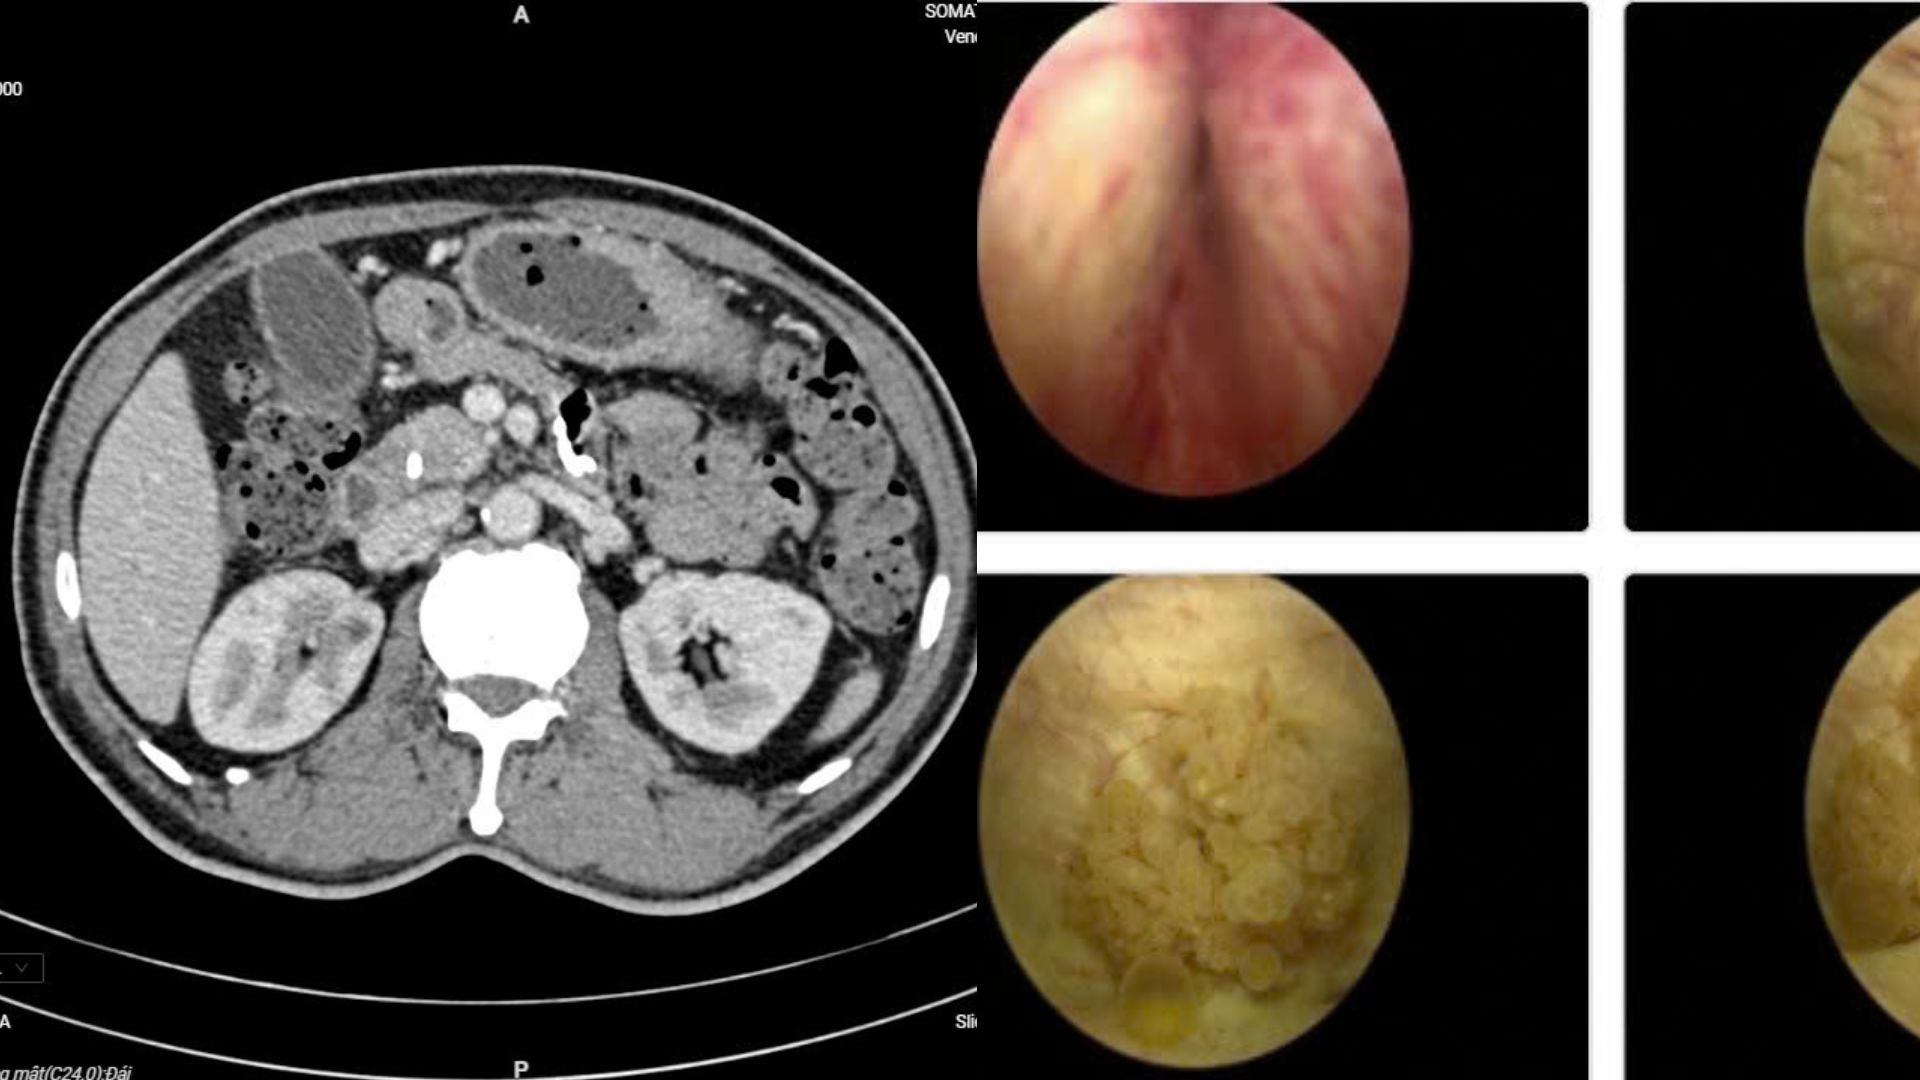

Người bệnh Đ.V.L nhập viện với biểu hiện đau bụng lâm râm kéo dài kèm vàng da nhẹ. Các xét nghiệm chuyên sâu và chẩn đoán hình ảnh cho thấy ông mắc đồng thời ung thư bàng quang và ung thư ống mật chủ – hai bệnh lý ác tính hoàn toàn khác biệt. Điều đáng nói là trước đó, người bệnh gần như không có dấu hiệu đặc trưng nào.

Các chuyên gia đã tổ chức hội chẩn liên chuyên khoa, thống nhất phương án phẫu thuật nội soi đồng thời cả hai bệnh ung thư. Đây là ca bệnh hiếm gặp, bởi việc can thiệp cùng lúc hai cơ quan khác nhau đòi hỏi trình độ chuyên môn cao và sự phối hợp chặt chẽ giữa nhiều chuyên ngành.

Ê-kíp gồm các chuyên khoa Tiết niệu, Gan mật tụy, Chẩn đoán hình ảnh và Giải phẫu bệnh đã phối hợp theo mô hình “teamwork”. Người bệnh được chỉ định cắt u bàng quang qua nội soi ngược dòng và phẫu thuật cắt khối tá tụy bằng nội soi ổ bụng.

Để chẩn đoán, người bệnh cần thực hiện xét nghiệm máu, nước tiểu, siêu âm hệ tiết niệu, chụp cắt lớp vi tính. Soi bàng quang là phương pháp quan trọng giúp đánh giá số lượng, vị trí, mức độ xâm lấn của khối u.